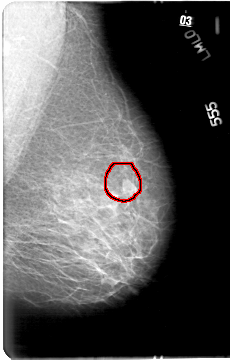

D_4033_1.LEFT_MLO

LEFT_MLO LINES 5386 PIXELS_PER_LINE 3436 BITS_PER_PIXEL 12 RESOLUTION 43.5 OVERLAY

FILE: D_4033_1.LEFT_MLO.OVERLAY

TOTAL_ABNORMALITIES 1

ABNORMALITY 1

LESION_TYPE MASS SHAPE IRREGULAR MARGINS ILL_DEFINED

ASSESSMENT 0

SUBTLETY 5

PATHOLOGY BENIGN

TOTAL_OUTLINES 1

BOUNDARY